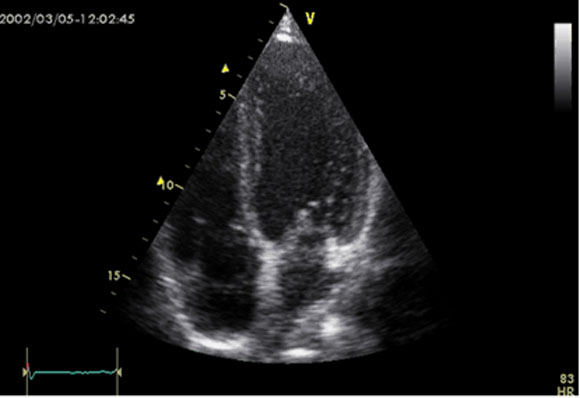

- 7 - Echocardiographie - Doppler